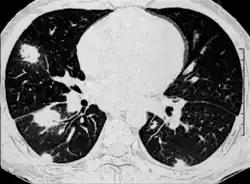

Fungal pneumonia is an infection of the lungs by fungi. It can be caused by either endemic or opportunistic fungi or a combination of both. Case mortality in fungal pneumonias can be as high as 90% in immunocompromised patients,[1][2] though immunocompetent patients generally respond well to anti-fungal therapy.

Diagnosis

Fungal pneumonia can be diagnosed in a number of ways. The simplest and cheapest method is to culture the fungus from a patient's respiratory fluids. However, such tests are not only insensitive but take time to develop which is a major drawback because studies have shown that slow diagnosis of fungal pneumonia is linked to high mortality.[4]

Microscopy is another method but is also slow and imprecise. Supplementing these classical methods is the detection of antigens. This technique is significantly faster but can be less sensitive and specific than the classical methods.[5]